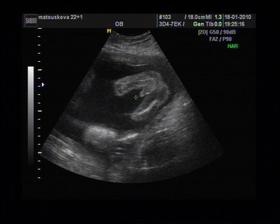

8/10 jsme se byli podívat u paní doktorky, zda testy nelhaly - a ono n e. Puclík měřil 0,37cm a co je důležité - srdíčko už funguje. Táta s Pepínem byli v ordinaci s námi, a když se na monitoru objevilo mimi, tak ho Pepíno pozdravil - udělal mu "ahoj" 🙂 oba nás to s Honzou dojalo. Další kontrola 22/10.